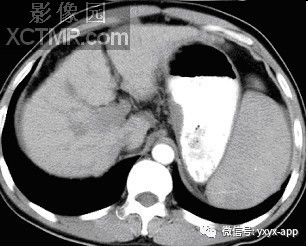

CT增强门脉期

【影像表现】X线吞钡:食管下段迂曲,管壁呈锯齿状改变,粘膜皱襞增宽、增粗,扭曲呈蚯蚓状,并可见串珠状充盈缺损,食管稍扩张,管壁轮廓凹凸不平,钡剂排空延迟。管壁柔软,舒缩功能良好。 CT平扫及增强扫描可见食管内多发类圆形稍低密度病灶,动脉期未见明显强化,门脉期强化明显,与同层面主动脉强化程度相仿,显示病灶为血管性病变。肝脏大小比例失调,肝表面结节样不平,肝内密度尚均匀,未见明显局灶性密度异常及异常强化。

CT:增强三维重建可以明确曲张的范围及程度,尤其对食管旁静脉曲张及静脉曲张硬化治疗后随访有一定价值。影像表现为管壁增厚,管腔不规则,常合并胃底静脉曲张,除食管黏膜下或食管旁区外,肝胃韧带区可以出现卵圆形或葡萄状软组织影,增强扫描可以显示明显强化的迂曲血管团,呈持续强化,延迟性强化。